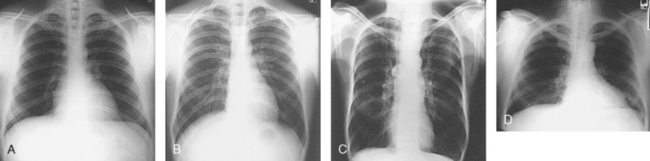

An organ such as the gallbladder may vary in position by 8 inches, depending on the body habitus. The stomach may be positioned horizontally, high, and in the center of the abdomen for one type of habitus and positioned vertically, low, and to the side of the midline in another type. Fig. 3-9 shows an example of the placement, shape, and size of the lungs, heart, and diaphragm in patients with four different body habitus types.

Fig. 3-9 Placement, shape, and size of lungs, heart, and diaphragm in patients with four different body habitus types. A, Sthenic. B, Hyposthenic. C, Asthenic. D, Hypersthenic.